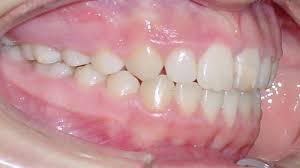

Der zahnwechsel von den milchzähnen zum bleibenden gebiss findet meist zwischen dem siebten und zwölften lebensjahr statt. Wann wachsen bei einem baby die ersten zähne? Er beginnt in der regel mit dem durchbruch des ersten großen backenzahns um das sechste lebensjahr herum. Ebenso wie bei den vorderen großen backenzähnen sind an deren stelle keine milchzähne vorhanden, so dass der durchbruch nicht merklich geschieht. Er verläuft oft unbemerkt, da die backenzähne hinter den milchbackenzähnen durchbrechen und dafür kein milchzahn ausfällt.

So Viele Zahne Hat Ihr Hund Alle Infos Vom Zahnwechsel Bis Zur Pflege Petplan from www.petplan.de Das sind breite mahlzähne weit hinten in der mundhöhle. Er beginnt in der regel mit dem durchbruch des ersten großen backenzahns um das sechste lebensjahr herum. Das kann der fall sein, wenn zähne oder zahngruppen nicht angelegt sind. Den ratten wuchsen die neuen zähne innerhalb von neun wochen nach. Die bleibenden backenzähne brechen häufig unbemerkt hinter den milchbackenzähnen durch. Wenn weisheitszähne wachsen oder anfangen durchzubrechen, verspüren viele betroffene ein mehr oder weniger stark ausgeprägtes druckgefühl im bereich der backenzähne. Darüber hinaus kann auch die bisslage den zahnwechsel stören. Wenn zähne auf der rechten und linken seite nicht zur gleichen zeit wachsen, sollten sie uns allerdings aufsuchen.

Ungefähr ab der sechsten woche sollten die welpen aufhören, bei der mutter zu saugen. Sie wachsen und üben somit druck auf die hinteren backenzähne aus. Er beginnt in der regel mit dem durchbruch des ersten großen backenzahns um das sechste lebensjahr herum. Zwischen 9 und 11 jahren fallen die temporären backenzähne aus. Bei den meisten menschen wächst noch ein dritter großer backenzahn auf jeder seite nach, wenn sie erwachsen sind.